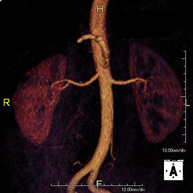

Prova diagnòstica no invasiva que consisteix en l'estudi de l'artèria aorta abdominal per obtenir imatges d'alta definició anatòmica mitjançant l'ús d'un camp electromagnètic i ones de ràdio (amb un emissor i un receptor). És indispensable l'ús de contrast intravenós paramagnètic (Gadolini). No obstant, no utilitza radiació ionitzant. La qualitat de les imatges permet realitzar reconstruccions en 2D i 3D. Està indicat en aquells pacients amb malaltia vascular (Aterosclerosi), per a l'estudi d'aneurismes, en estudis prequirúrgics de lesions adjacents a l'aorta abdominal com "mapa" vascular, etc. - Angio-RM Aorta ilíaca

Prova diagnòstica no invasiva que consisteix en l'estudi de l'artèria aorta abdominal per obtenir imatges d'alta definició anatòmica mitjançant l'ús d'un camp electromagnètic i ones de ràdio (amb un emissor i un receptor). És indispensable l'ús de contrast intravenós paramagnètic (Gadolini). No obstant, no utilitza radiació ionitzant. La qualitat de les imatges permet realitzar reconstruccions en 2D i 3D. Aquesta prova està especialment indicada com estudi prequirúrgic (mapa vascular) abans d'intervencions percutànies o quirúrgiques d'aorta abdominal, per a l'estudi complementari en pacients amb isquèmia de membres inferiors, etc. - Angio-RM d'Artèries renals